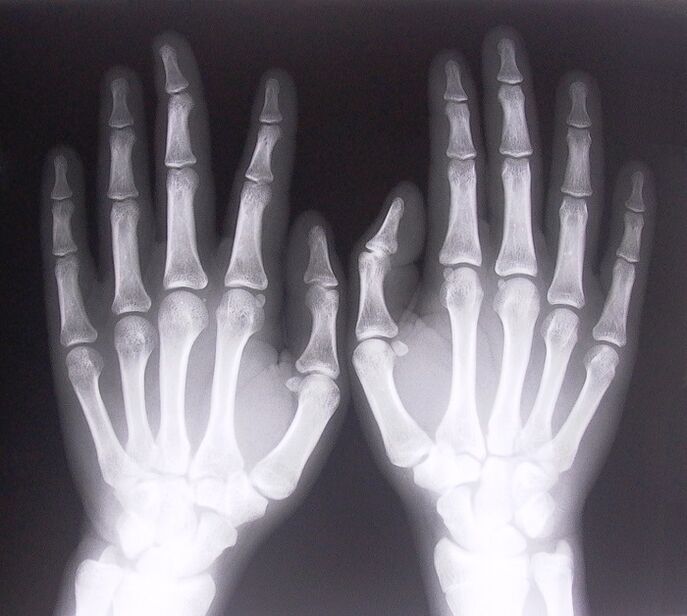

- Ligamentite sténosante. Pour identifier la cause de la maladie, il est nécessaire de subir une radiographie. Les symptômes sont typiques : mouvement douloureux de la main, boucle de la paume serrée. De plus, lors de l'extension, des clics se font généralement entendre.

- Prenez des radiographies.